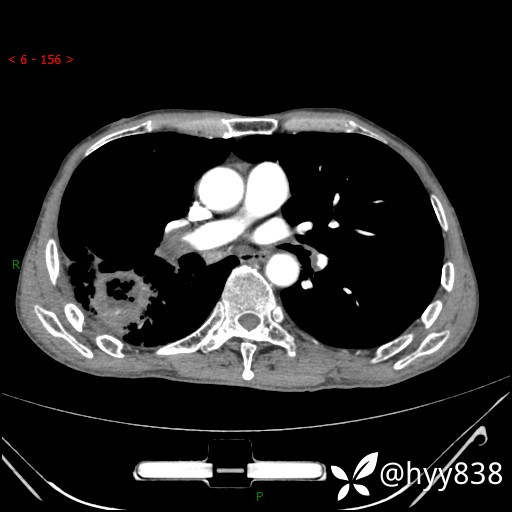

增强动脉期